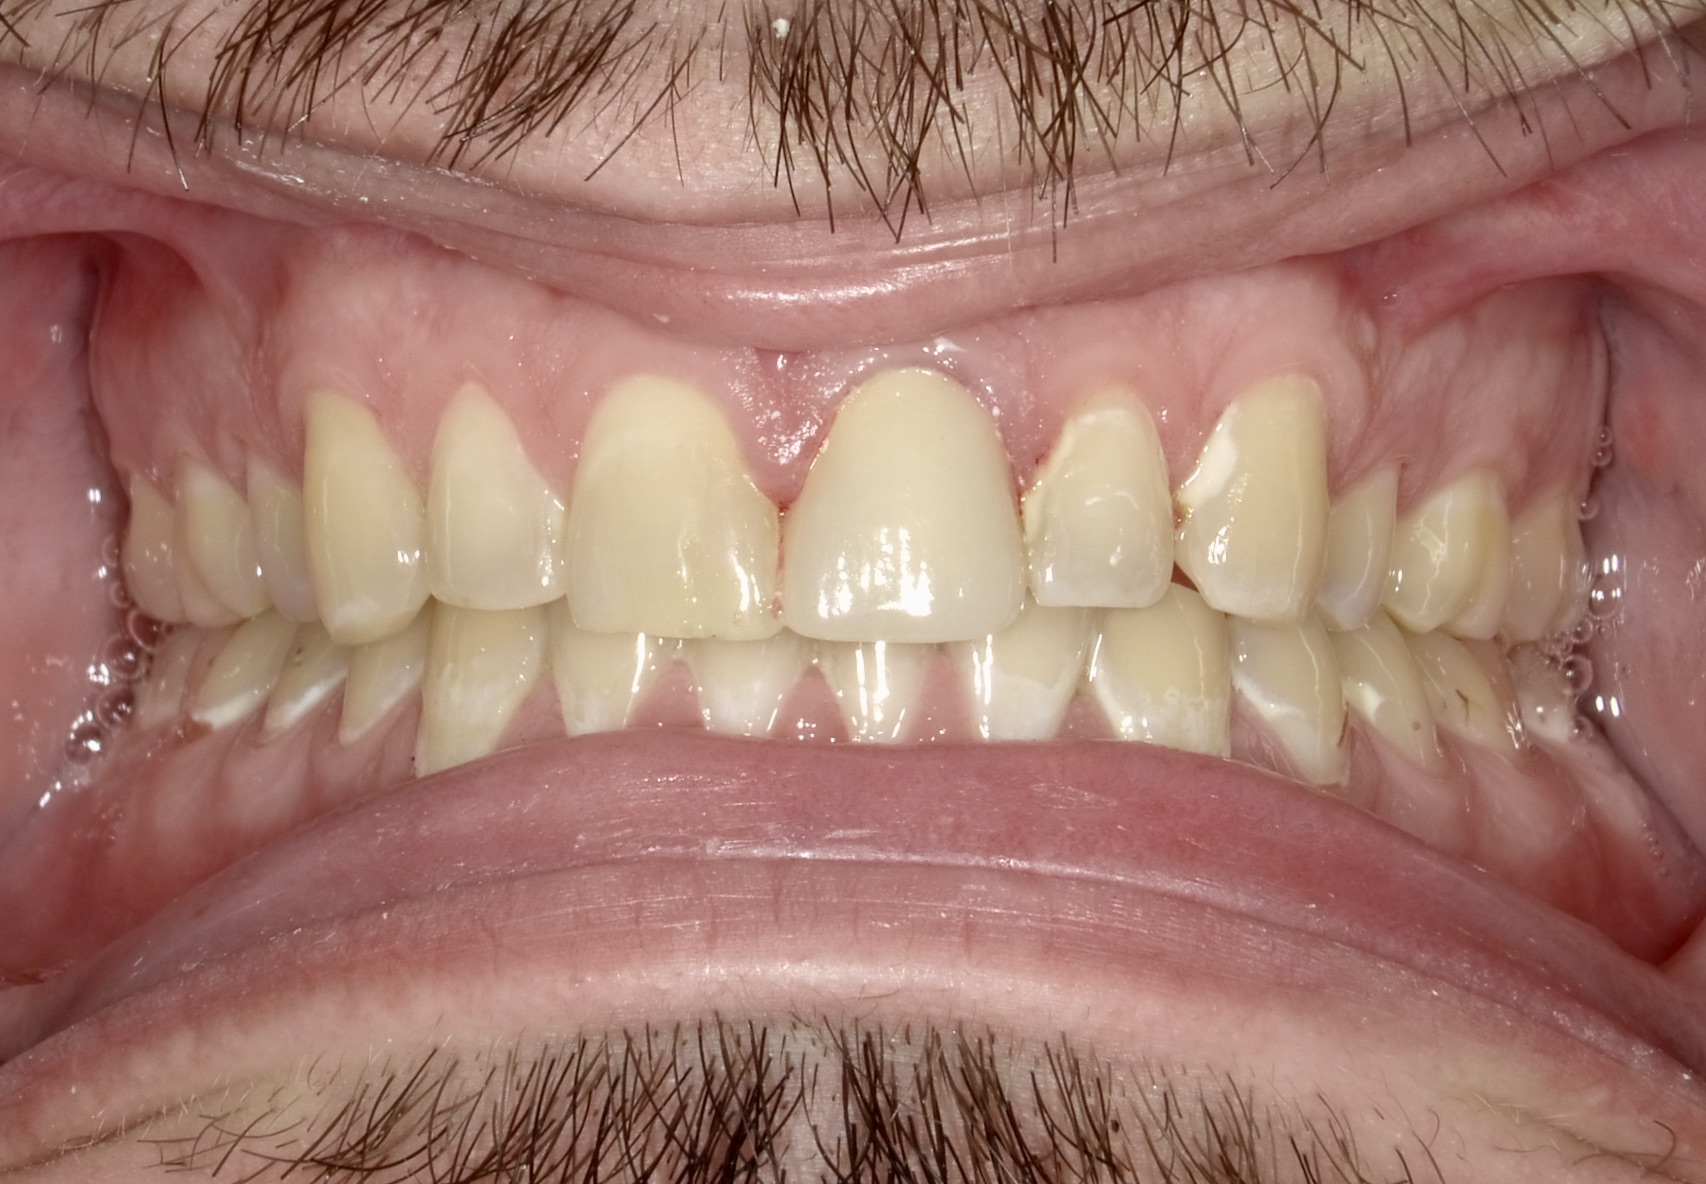

Fig 2. Extra-oral photography. All dental practices should provide the patient with the following four extra-oral photographs: the close-up smile (Fig 1), the retracted smile (Fig 2), the upper arch (Fig 3), and the lower arch (Fig 4).

Figure 2

Extra-oral photography. Extra-oral photography is essential for giving patients a full picture of their smile and oral health status. This has been a challenge for most dentists over the past two decades because many cameras that have the capability of taking high-quality, fully focused images of the dental arch have been difficult to use and program and awkward to sterilize. Other dentists have limited their use of such cameras to the occasional cosmetic case. However, extra-oral photography should be provided for every patient. The use of such photography and the type of photographs taken can vary from office to office, depending on the patient flow and the availability and training of personnel at that particular office. Regardless of these variations, however, all dental practices should take the following four extra-oral photos: the close-up smile, the retracted smile, the upper arch, and the lower arch (Figure 1 through Figure 4).